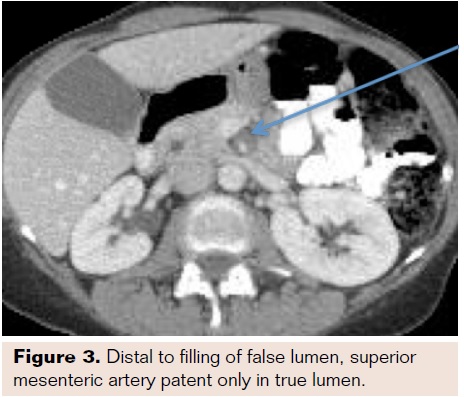

Abdominal exam revealed focal tenderness in the suprapubic region without rebound or guarding. There was no purpura or other abnormal skin findings. Vasculitis workup was not undertaken. A CT of the abdomen was performed, which showed SMA dissection within 1 centimeter from the takeoff and cecal wall thickening without signs of ischemia (Figures 1-3). No other dissection or vascular abnormality was noted. She was admitted to the vascular surgery service, made NPO, and started on a heparin infusion as well as ciprofloxacin and metronidazole for the typhlitis.

A

dedicated CT angiography of the abdomen was performed 24 hours after the initial CT due to the contrast load received on admission (as per institutional policy). The repeat scan was significant for long segment dissection of the SMA with focal contrast filling of the false lumen and a “mild-moderate” narrowing of the true lumen, which was most prominent in the mid portion of the vessel. All branches of the SMA arose from the true lumen, and again, the cecum was noted to be inflamed without pneumatosis. The patient’s abdominal exam improved over the next few days, and she was discharged home on hospital day 4 tolerating a regular diet. She was instructed to finish a course of antibiotics and to start taking warfarin after bridging with fondiparinux.